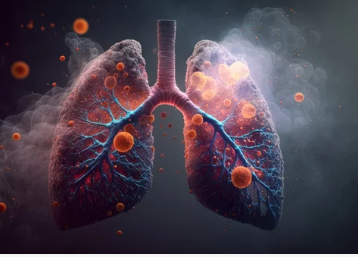

2. 폐결핵의 진행 단계별 증상 차이

| 초기 (1~2주) | 폐에 염증 시작, 면역 반응 진행 | 마른기침, 피로, 미열 |

| 중기 (3주 이상) | 폐조직 손상, 염증 확산 | 가래 기침, 야간 발한, 식욕저하 |

| 말기 (진행형 결핵) | 폐포 파괴, 객혈 및 전신 침범 | 심한 체중감소, 빈혈, 흉통 |